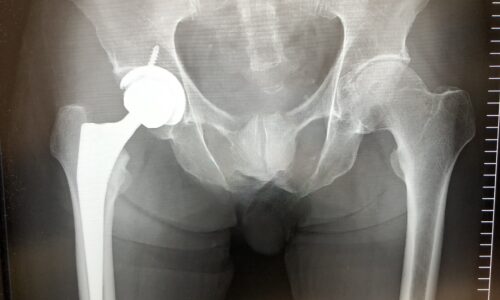

右脚人工股関節手術後10日目初めての外来検診と執刀医との問答

本日は退院後初めての外来検診です。術後10回目、退院後6日目です。昨日は午後あたりから杖なしでも歩けるようになり駅の階段の上り…